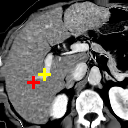

Refer to caption

(a)

(b)

(c) 2.06

(d) 0.9414

(e) 2.10

(f) 0.9408

(g) 2.46

(h) 0.9211

(i) 2.18

(j) 0.9439

(k) 2.27

(l) 0.9345

Figure 8: Example comparison among VTN ADD (c/d), VTN DD(e/f), Elastix (g/h), ANTs (i/j) and VoxelMorph-2(k/l). The input images to methods with “” are affinely aligned to a fixed atlas by ANTs and their warped images are transformed backwards according to the affine transformation aligning the fixed image and the atlas for sensible comparison. Columning and coloring are the same as those in Figure 6, except that the fixed image and the moving image are a pair of MR brain scans and that the landmarks are L7, L12 and L15. Best viewed in color.